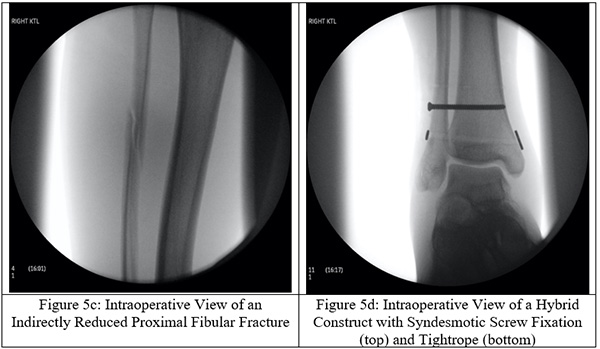

Surgical intervention is a definitive form of treatment for ankle instability and the associated fibular fracture. The proximal fibular fracture is not directly stabilized, but instead indirectly stabilized through fixating the distal fibula to the tibia with trans-syndesmotic screws (Figures 5a-f). To restore the fibular length, the distal end of the fibula is elongated into its anatomical position for trans-syndesmotic fixation. Other stabilization techniques have been described in the literature such as the use of bioabsorbable screws, syndesmotic staples, circular wire external fixators, Kirschner wires, flexible implants, syndesmotic hooks, syndesmotic bolts, and cerclage wires.[12] Metal screw fixation or a suture loop between two buttons, or some combination of the two, still stands to be the most popular choice among orthopedic surgeons. Use of screws carries the downside of requiring an additional surgery to remove the screws but may be more effective at maintaining length. By utilizing these screws, the fibular length is properly restored and the ankle mortise is appropriately reestablished. Suture loops between buttons (the ankle “tightrope”) has the advantage of not requiring screw removal but may not be as effective at maintaining fibular length.